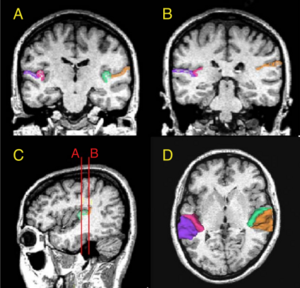

Magnetic Resonance Imaging and 3-Dimensional Analysis of External Anal Sphincter Anatomy

Publication: Obstet Gynecol. 2005 Dec;106(6):1259-65. PDF

Authors: Hsu Y, Fenner DE, Weadock WJ, DeLancey JO

Institution: Pelvic Floor Research Group, Division of Gynecology, Department of Obstetrics and Gynecology, University of Michigan, Ann Arbor, Michigan 48109-0276, USA.

Background/Purpose: To use magnetic resonance images of living women and 3-dimensional modeling software to identify the component parts and characteristic features of the external anal sphincter (EAS) that have visible separation or varying origins and insertions. METHODS: Detailed structural analysis of anal sphincter anatomy was performed on 3 pelvic magnetic resonance imaging (MRI) data sets selected for image clarity from ongoing studies involving nulliparous women. The relationships of anal sphincter structures seen in axial, sagittal, and coronal planes were examined using the 3-D Slicer 2.1b1 software program. The following were requirements for sphincter elements to be considered separate: 1) a clear and consistently visible separation or 2) a different origin or insertion. The characteristic features identified in this way were then evaluated in images from an additional 50 nulliparas for the frequency of feature visibility. RESULTS: There were 3 components of the EAS that met criteria as being "separate" structures. The main body (EAS-M) is separated from the subcutaneous external anal sphincter (SQ-EAS) by a clear division that could be observed in all (100%) of the MRI scans reviewed. The wing-shaped end (EAS-W) has fibers that do not cross the midline ventrally, but have lateral origins near the ischiopubic ramus. This EAS-W component was visible in 76% of the nulliparas reviewed. CONCLUSION: Three distinct external anal sphincter components can be identified by MRI in the majority of nulliparous women.

Grant Support:

- P50 HD4406

- R01 HD38665